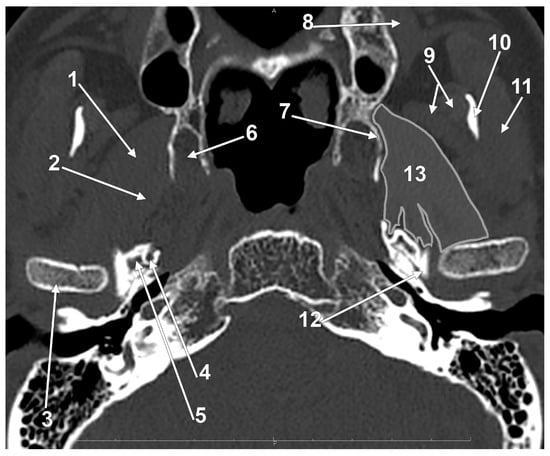

4.2.3. The Lateral and Medial Bundles of the Inferior Head of the Lateral Pterygoid Muscle

4.2.4. Nerves, Arteries, and the Lateral Pterygoid Muscle